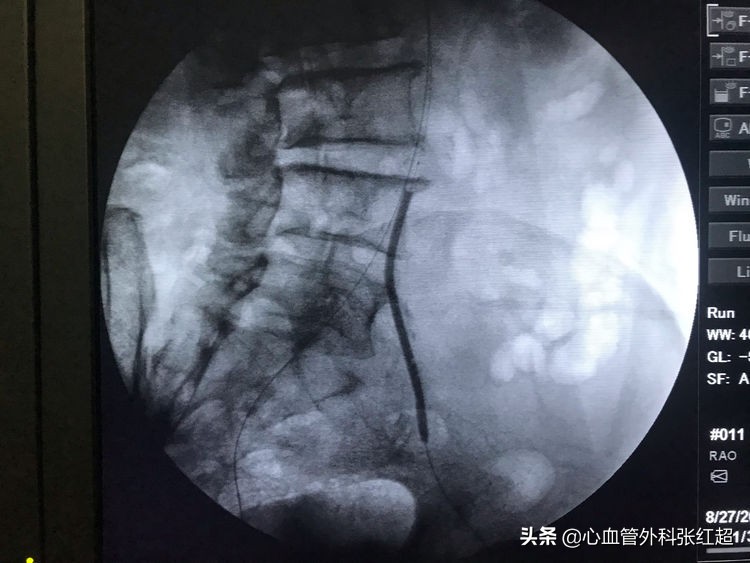

扩张中患者有痛应终止,防心弯曲部分球囊肩撕性撕裂。

血管造影剂排空快,对侧显影淡,说明血管内血流速度快。

屈曲部稍有残余狭窄。不用硬扩,支架可以在术后贯性序扩。